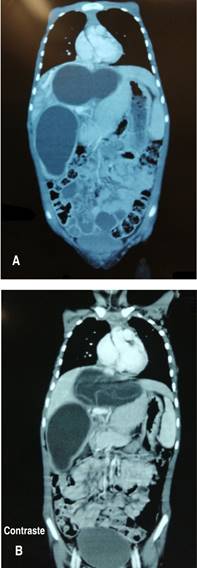

Se le realiza una tomografía de cuerpo entero. En abdomen en la vista coronal se observaron dos imágenes quísticas en hígado con edema adyacente, una ubicada entre segmento V-VI circunferencial, que midió 70 × 60 × 105 mm; la segunda, se localizaba en el lóbulo hepático izquierdo con membranas desprendidas, con dimensiones de 110 × 56 × 51 mm (Figuras 3 y 4).

Figura 4: A y B) Vista coronal de la tomografía de abdomen con contraste y sin contraste. Se observan dos imágenes quísticas gigantes en lóbulo hepático derecho e izquierdo.

Por otra parte, en el tórax también se identificó una imagen quística en segmento posterior del lóbulo superior derecho de 30 mm de diámetro, con membranas desprendidas hiperdensas en su interior.